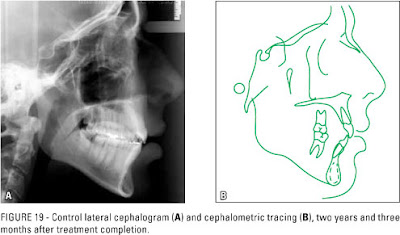

* X quang chẩn đoán được phân tích tỉ mỉ thông qua phim sọ nghiêng nhằm để khẳng định sau cùng trước khi đưa ra quyết định có hay không nên nhổ răng, tất cả dữ liệu này là bằng chứng y học giúp nha sĩ tổng quát hay chuyên khoa tự tin hơn trong quyết định của mình cũng như là hồ sơ pháp lý đối với nhà quản lý y tế có trách nhiệm.

– Hình ảnh Xquang toàn diện, sọ nghiêng, sọ thẳng

X Quang sọ nghiêng phân tích